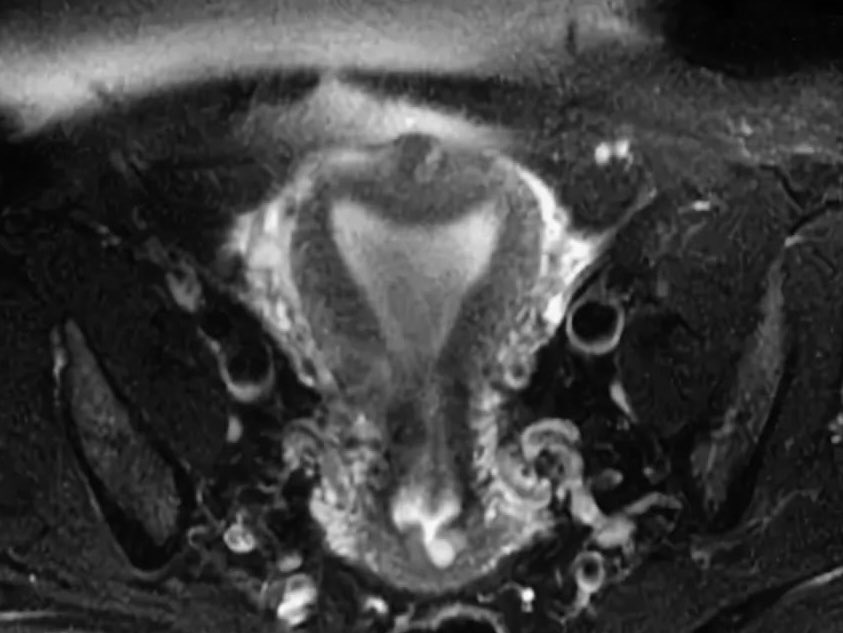

Двух рогая

Двух рогая 108 фото